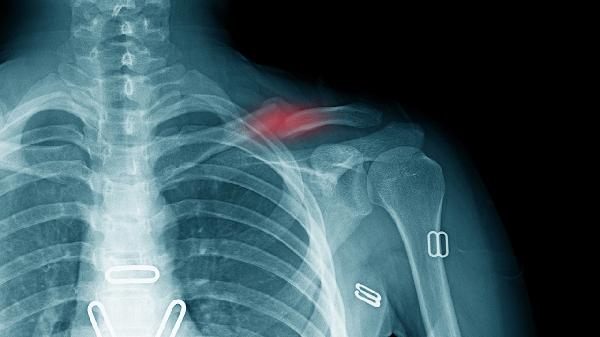

孟氏骨折发生在尺骨近1/3处,伴随桡骨头向前、外侧脱位。盖氏骨折位于桡骨远端1/3,合并下尺桡关节脱位或三角纤维软骨复合体损伤。X线检查中,孟氏骨折可见尺骨骨折线向桡侧成角,盖氏骨折显示桡骨短缩畸形。